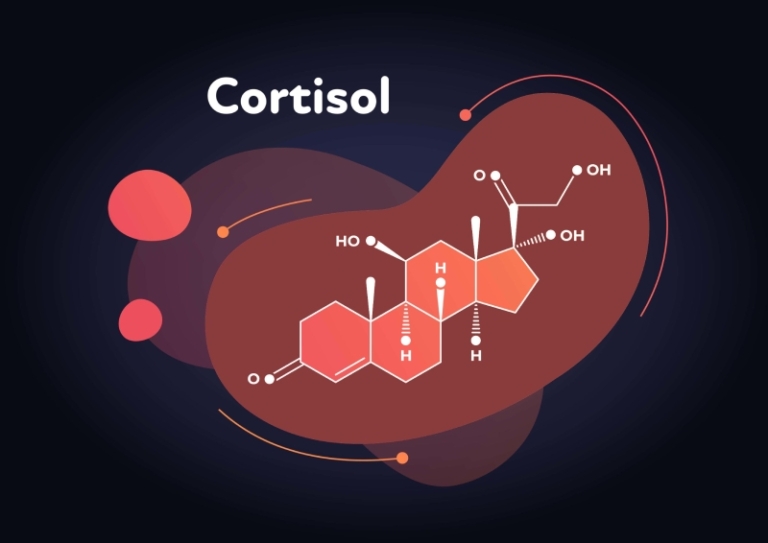

کورتیزول: هورمون حیاتی یا ابزار سوء استفاده تبلیغاتی؟

کورتیزول یکی از هورمونهای حیاتی بدن است که نقش کلیدی در حفظ سلامت جسم و روان ایفا میکند. این هورمون که توسط غدد فوقکلیوی ترشح میشود، به تنظیم